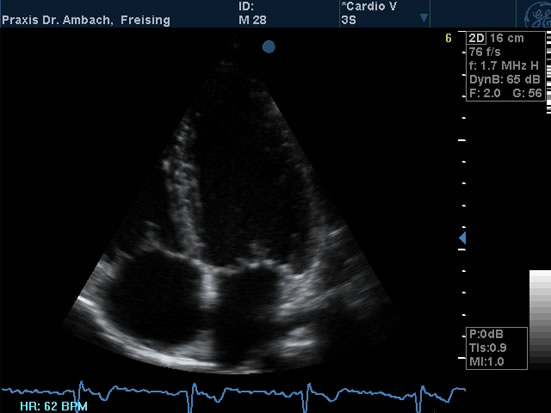

Echokardiographie